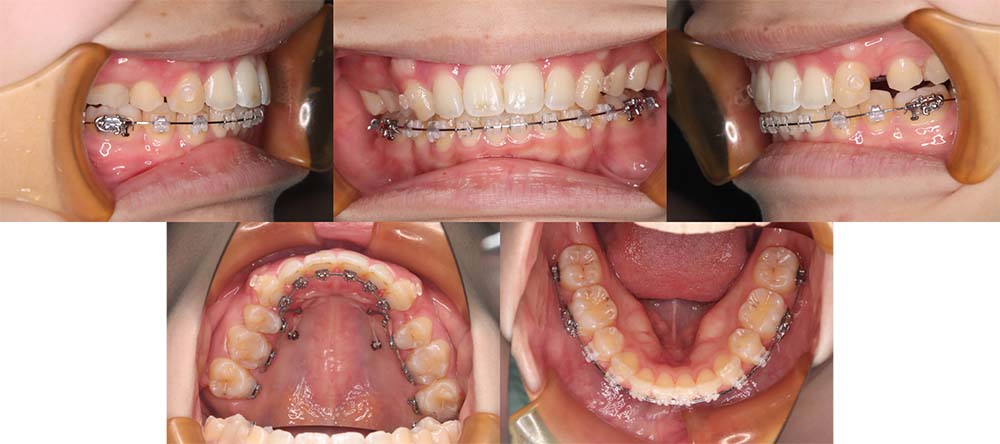

| 症例分類 | 上顎前突、口唇突出 |

| 診断名 | 左下4先天欠損を伴う上下前歯部叢生と骨格性上顎前突 |

| 主訴 | 出っ歯、下の歯がガタガタ、乳歯が1本ある |

| 年齢 | 31歳4ヶ月 |

| 性別 | 女性 |

| 抜歯部位 | 上の左右第一小臼歯と右下第二小臼歯と左下第二乳臼歯(4本) |

| 使用装置 | 上下裏側のワイヤー装置 |

| 治療期間 | 2年9ヶ月 |

| 保定装置 | 固定式保定装置、取り外し式保定装置(8時間) |

| 費用 |

[検査・診断料] ¥49,500 [基本施術料] ¥1,331,000 [調整料] ¥5,500/回 [抜歯] ¥5,500/本 [保定装置] ¥55,000(税込) 抜歯や虫歯治療は他院にて費用が別途かかります。(抜歯¥4,000〜10,000/本)

左下の永久歯が先天欠損で子供の歯が残っていて、その歯が抜けそうになったこともあり、矯正治療を考えて来院されました。

上下叢生と口唇閉鎖不全のため上下の抜歯をして治療をしました。下顎左側乳歯を抜去して治療をしました。

歯の動きが少しゆっくりだったため、予定より治療期間が伸びてしまいましたが問題なく咬合させることができました。